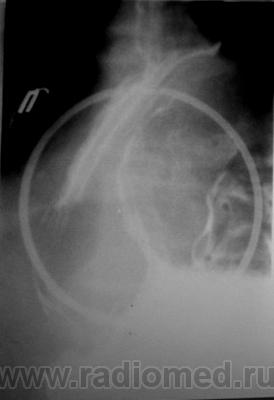

Наблюдение Морозова А.И. Фиксированная параэзофагеальная грыжа пищеводного отверстия диафрагмы

Фиксированная параэзофагеальная грыжа пищеводного отверстия диафрагмы.

Рентгеноскопия желудка (верхнего отдела желудочно-кишечного тракта): Акт глотания не нарушен. Пищевод свободно проходим до нижней трети грудного отдела, ниже определяется задержка продвижения контраста; контрастированный участок значительно расширен, создаётся впечатление, что последний является кариофундальным отделом желудка. Сам пищевод не укорочен, переходит в желудок в обычном месте.

Желудок: в вертикальном положении кардиофундальный отдел расположен в средостении (фиксирован), форма не изменена, смещаемость части желудка, расположенной в брюшной полости свободная. Складки слизистой прослеживаются на всём протяжении, ровные. Перистальтика глубокая, начальная эвакуация своевременная .12-перстная кишка и начальные петли тощей кишки без особенностей.

Фиксированная параэзофагеальная кардиофундальная грыжа пищеводного отверстия диафрагмы.